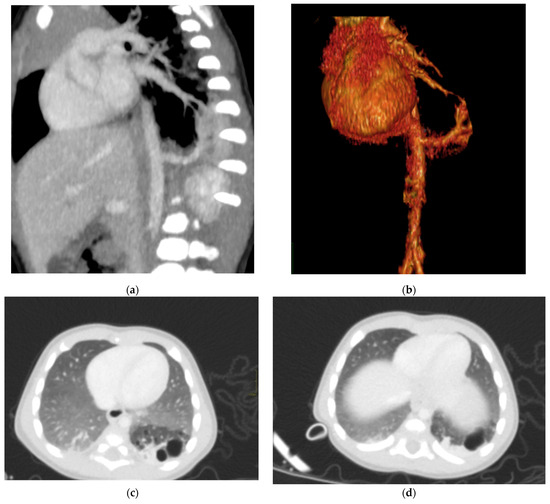

In terms of location, about 85–90% of sequestrations are supradiaphragmatic, with the remaining 10–15% being subdiaphragmatic [11]. Approximately 90% of sequestrations are located on the left side. The systemic arterial supply typically comes from both the lower thoracic and upper abdominal aorta (Figure 6).

Figure 6. Hybrid congenital malformation consisting of lung seizure and CCAM. CECT MPR reconstruction (a), VR (b), and axial (c,d) images show the presence of a lobulated-margin formation located in the lower lobe of the left lung, which is consists of multiple cystic formations (diameters ranging between a few millimeters and 1.5 cm) and a consolidation zone corresponding the costodiaframmatic recess, which is supplied by a voluminous arterial branch originating from the left lateral wall of the aorta in the thoraco-thoracic passage.